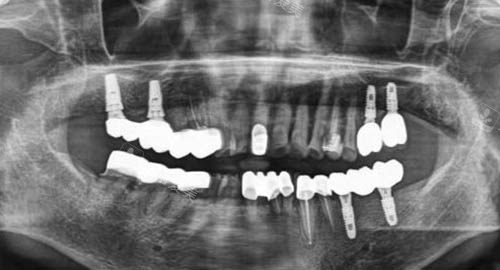

新型的口腔 CT 设备能够提供高清晰度的口腔内部图像,帮助医生更比较准地诊断病情。

在种植手术中,新型的种植导航系统可以精细引导种植体的植入位置,提高种植的成功概率。